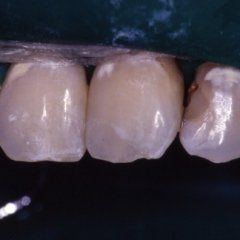

L’enorme diffusione ancora oggi riscontrabile della carie dentaria, unita a traumi, difetti di mineralizzazione o ipoplasie dello smalto determinano la necessità di dover ricorrere ad un restauro dei tessuti dentari lesionati. Il continuo miglioramento dei materiali e di conseguenza delle tecniche hanno altresì ampliato il raggio di azione della cosiddetta conservativa che con il ricorso al trattamento endodontico in caso di lesioni particolarmente gravi, occupa circa i due terzi dell’attività del dentista. In considerazione di questo fatto quindi, oltre all’evidenza che il trattamento restaurativo diretto è in genere il primo atto odontoiatrico che si effettua su una corona dentale lesionata, emerge la necessità che questa terapia sia ben eseguita ed in armonico rapporto con le strutture parodontali ed endodontiche.